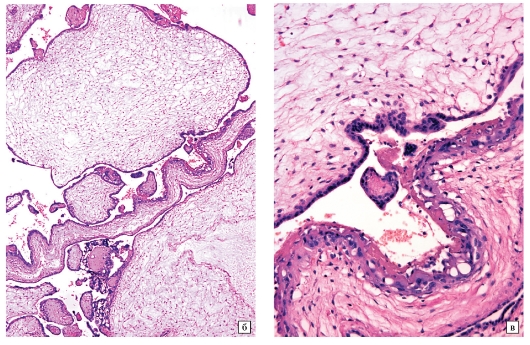

а - Микропрепарат частичного пузырного заноса при небольшом увеличении: увеличенные ворсины плаценты с отеком стромы, неровность краев ворсин и трофобластические включения в их строме.

Пролиферация трофобласта минимальная

б - Микропрепарат ворсин частичного пузырного заноса при большом увеличении:

в строме мелкие сосуды, содержащие эритроциты плода с ядрами

Патоморфологические признаки ЧПЗ могут быть едва заметны и поэтому плохо диагностироваться. Отмечают локальную или различную степень гид-ропической дистрофии ворсин с неровностью краев и трофобластическими включениями. В отличие от ППЗ локальная пролиферация трофобласта выражена слабо. При ЧПЗ в сосудах ворсин имеются фетальные эритроциты или обнаруживается нежизнеспособный плод, возраст которого редко превышает 20 нед. беременности.